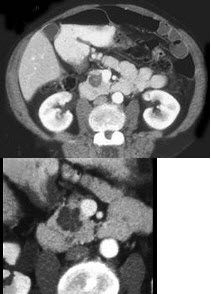

女性,34岁,寒战、高热、急性中上腹偏左腹痛,压痛,CT扫描如图,最可能的诊断是( )

A:急性胰腺炎

B:胰腺脓肿

C:慢性胰腺炎急性发作

D:胰腺癌

E:胰腺转移癌